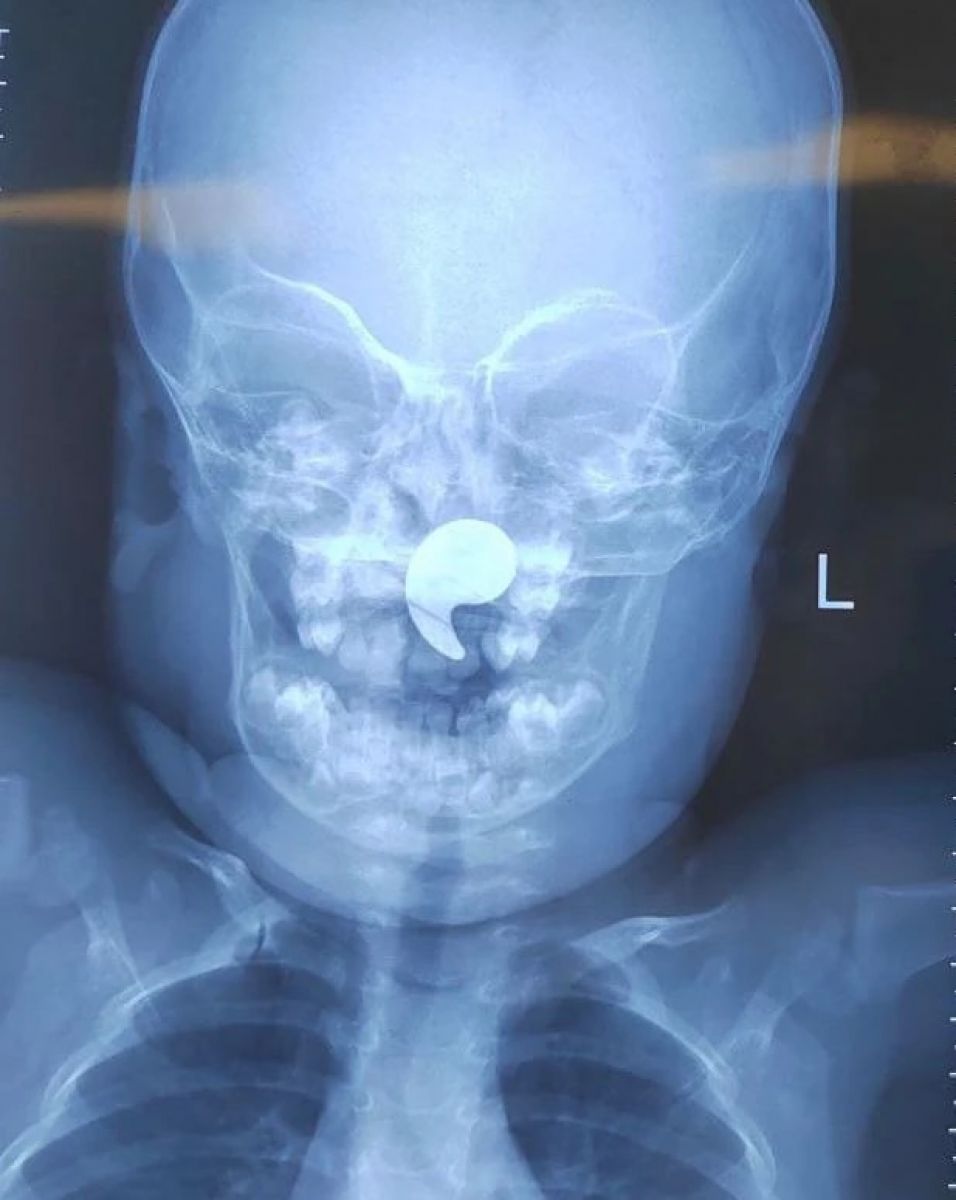

Малышке сделали рентгеновский снимок и подтвердили наличие инородного тела. Ребенка госпитализировали в оториноларингологическое отделение. Под общим наркозом и под контролем эндоскопа магнит был успешно извлечен. Уже на следующие сутки девочку выписали домой под наблюдение педиатра.